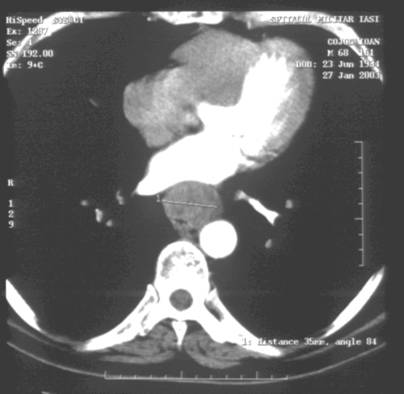

Figure 1. CT evaluation of a locally advanced

esophageal cancer